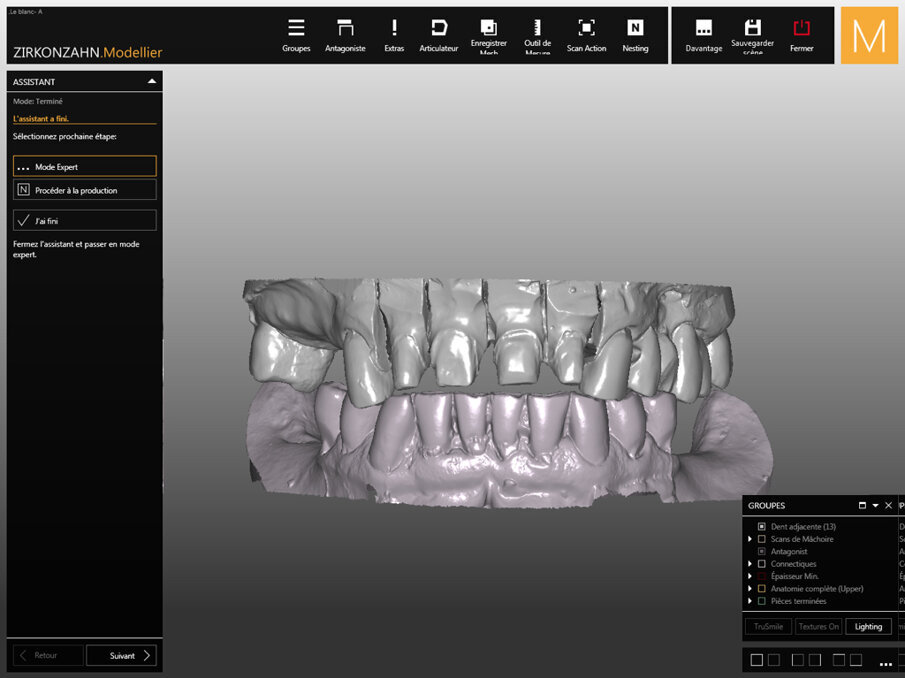

Captured four days earlier, Figure 6 shows the digital wax-up performed in Zirkonzahn.Modellier software (Zirkonzahn). For the dental technician, the main difficulty was rethinking the anatomy of the maxillary incisors while restoring the initial shape of the teeth. The overall shape of the other teeth gives an overview of the geometric typology of the teeth: round, square, triangular.

All forms are possible, but only one form is suitable for this clinical case. CAD/CAM software allows automatic guidance in obtaining a harmonious shape. Then the laboratory technician will take control and proceed individually to bring human touches to a computer system.

Captured five days earlier, Figure 7 shows the virtual model after the digital scan step (Zirkonzahn.Scan, Zirkonzahn). The software makes it possible to digitize physical models to import them into the software suite. The digital models are then mounted in occlusion on a virtual articulator. The preparation boundaries are drawn, and thanks to prior trimming, each prepared tooth can be individualised to move on to the next crown modelling step.